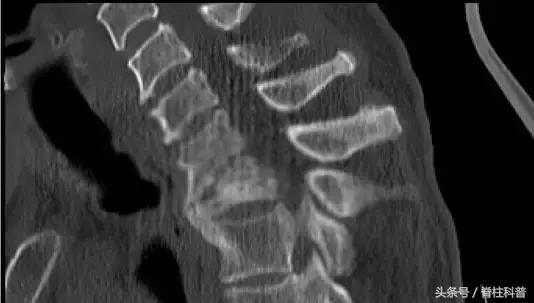

腰腿痛部分相关疾病图示

脊柱结核

骨质疏松压缩性骨折